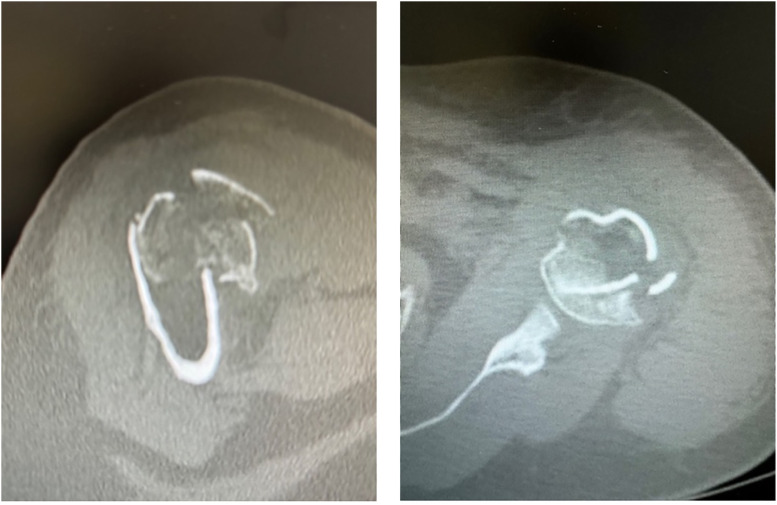

Results: Mean final CMS for this cohort was 80 points. The greater tuberosity healed in the anatomic position in 90% of the cases (N = 36), obtaining an average CMS of 80 in these patients. Healing of the greater tuberosity did not occur in 10% of the cases (N = 4), obtaining an average CMS of 60. All patients scored above 100° in forward elevation with a mean of 140°. Mean active external rotation was 30°. Low-grade scapular notching was reported in <1% of the cases. Major complications were reported in one patient with an acromial fracture. No complications or loosening of stem locking screws were noted. There were no reoperations.

Abstract Image